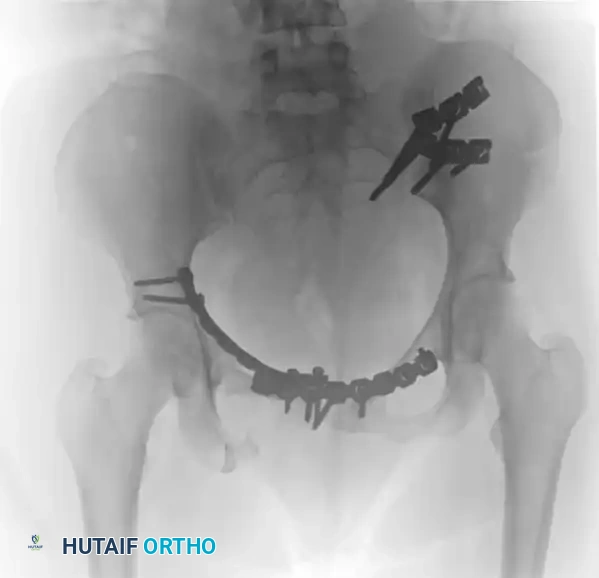

Image

FIGURE 56-52: Ganz “antishock” pelvic fixator for immediate, provisional stabilization of hemodynamically unstable pelvic fractures.

Application and Contraindications

• Landmarks: The intersection of a line drawn along the axis of the femur and a line drawn posteriorly from the ASIS.

• Application: The pins are driven to the outer table of the ilium, and the clamp is tightened to compress the SI joints.

• Contraindications: We firmly believe that an iliac wing fracture close to the sacroiliac joint (crescent fracture) is an absolute contraindication to the use of this device. Applying compression across a fractured iliac wing will cause medial displacement of the fracture fragment into the true pelvis, potentially lacerating the iliac vessels or lumbosacral plexus. Furthermore, highly comminuted transforaminal sacral fractures may over-compress, leading to severe sacral nerve root crush injuries.

• Duration: The Ganz C-clamp is strictly a temporary stabilizing device. It should be removed within 5 days, transitioning to definitive internal fixation once the patient is physiologically optimized.